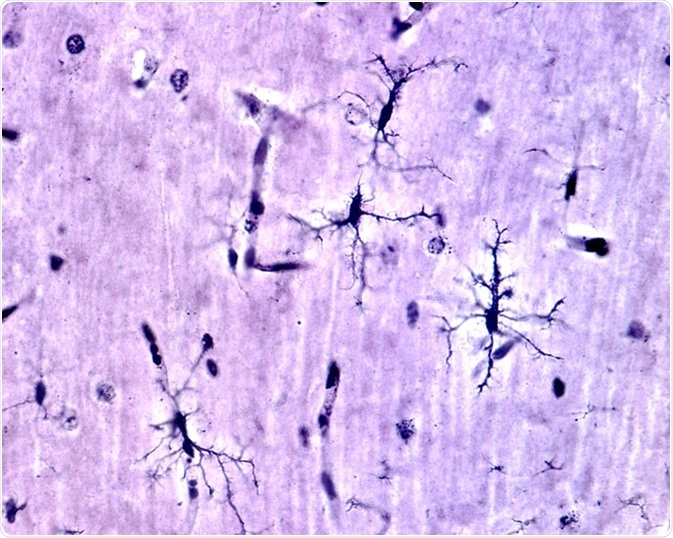

Microglia cells stained with Rio Hortega

Microglia cells stained with silver carbonate method in the grey matter of the brain. This type is the ramified or "resting" microglia that appears in normal brain tissue. - Image Credit: Jose Luis Calvo / Shutterstock

Resting microglia have a ramified appearance with small cell bodies and long branching processes that do not phagocytose cells or secrete immune factors.

Upon activation they become reactive (upregulation of Iba1) and can adopt an amoeboid state that is characterised by a large cell body with antigen presentation (like macrophages) and with thicker retracted branches.